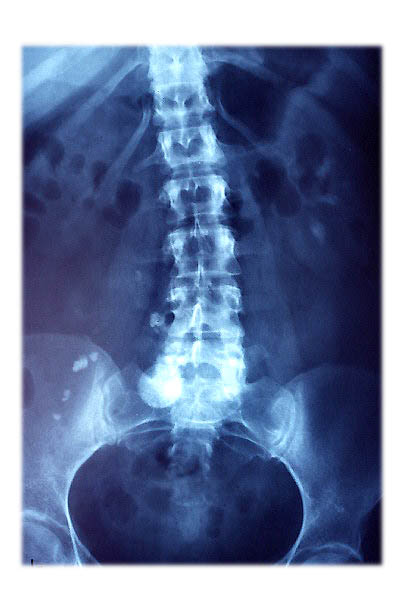

Escoliosis. Espondilolistesis.

Artrosis lumbar con pinzamiento.

Artrosis lumbar

Escoliosis, artrosis, aplastamiento...